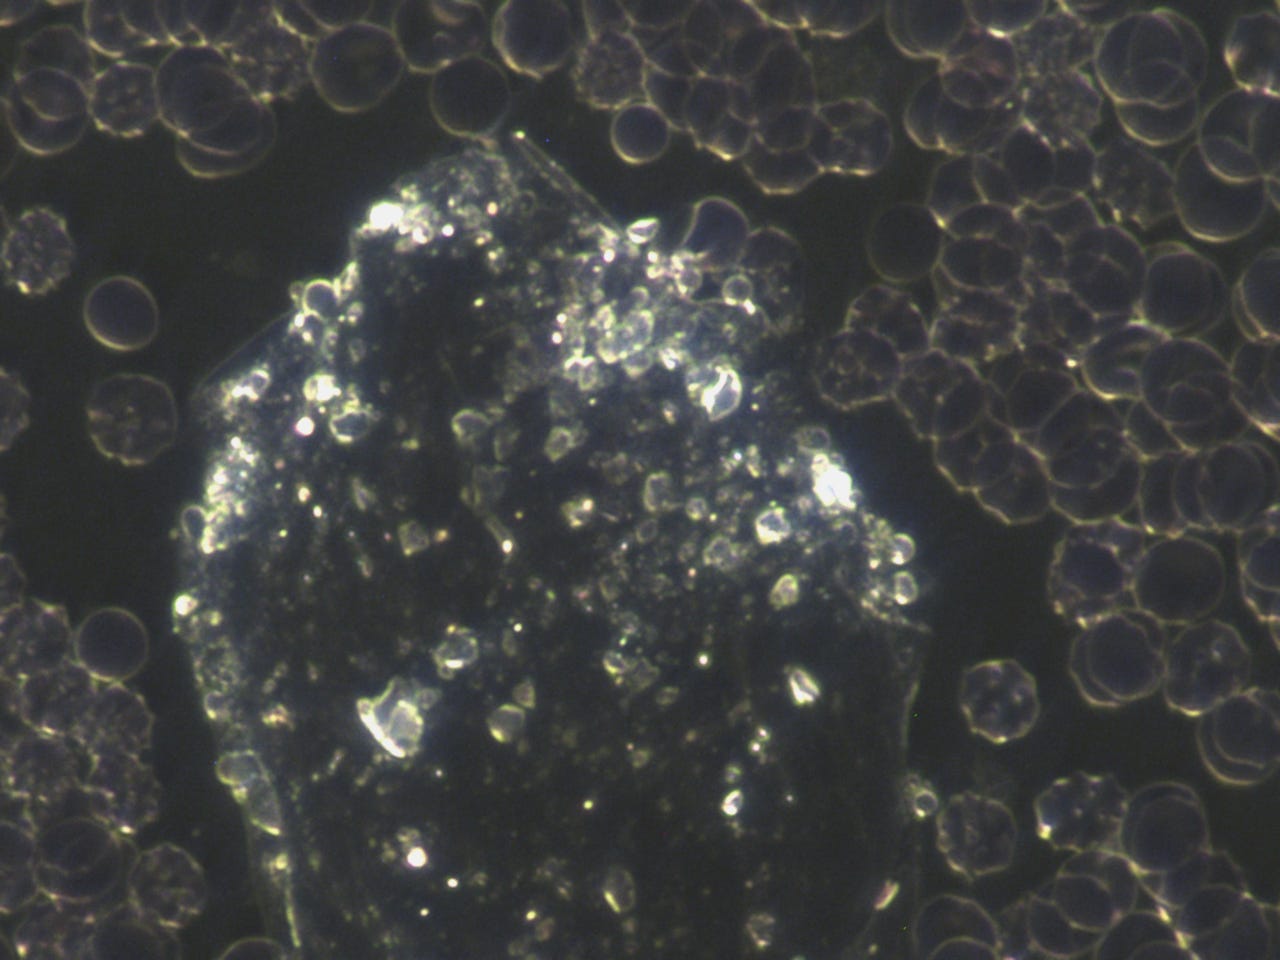

subscribed. Thank you so much. He asked to see my blood before the frequency treatments. The photo’s posted in the previous posts, especially the ones that showed the quantum dots in my blood after the MAH (Major Auto Hemotherapy) with ozone was before the frequency treatments. I am posting them here again, however, I will post some prior to that also.Quantum dots in my blood from Heparin pharmaceutical:

This was the morning after all the quantum dots destroyed my blood: